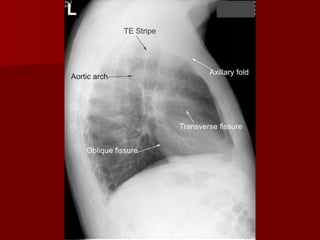

Oblique fissure more clearly seen on Lateral view from

T4-T5 vertebrae to reach the diaphragm and 5 cm

behind the costophrenic angle on left And just behind

the angle on right.

Horizontal fissure more clearly Seen on P.A view

extending from Right hilum to 6th rib in the axillary line

Horizontal Fissure

Right Oblique Fissure

Left Oblique Fissure